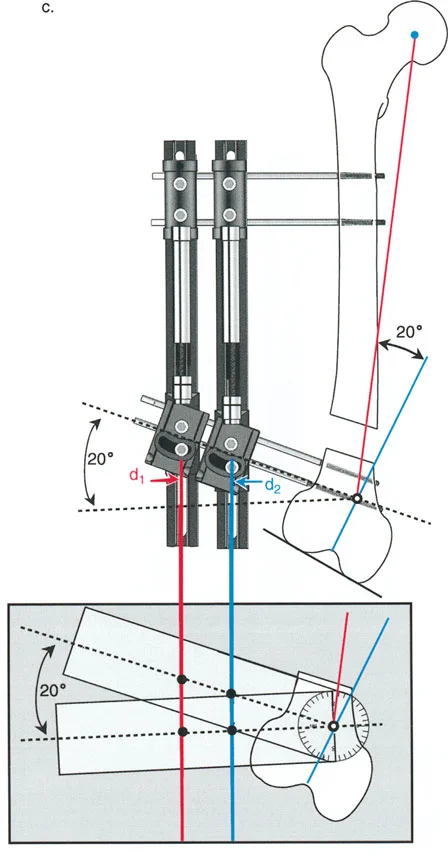

تحدي مركز دوران الانحراف (CORA) القريب من المفصل

لمطابقة مفصلة المثبت الخارجي مع المستوى الدقيق لمركز دوران الانحراف (CORA)، يجب غالبًا بناء المفصلة فوق أو تحت مستوى الحلقة الفعلية. يُعرف هذا في مبادئ بالي باسم تجميع المفصلة القريبة من المفصل (juxta-articular hinge assembly).

إذا كان مركز دوران الانحراف (CORA) يقع بالقرب من خط المفصل، فإن وضع حلقة إليزاروف القياسية عند هذا المستوى بالضبط مستحيل دون انتهاك مساحة المفصل أو شد الهياكل الكبسولية الحيوية. لذلك، يتم تثبيت الحلقة المرجعية بالعظم الكثيف أو العظم الطويل المتاح، ويتم بناء آلية المفصلة باستخدام قضبان ملولبة، ولوحات توصيل، ودعامات. ثم يتم "إنزالها" (أو رفعها) لتتطابق تمامًا مع مركز دوران الانحراف (CORA) الهندسي الحقيقي.

في المنشآت القريبة من المفصل، غالبًا ما نعتمد على قاعدة قطع العظم 2. نظرًا لأنه لا يمكننا قطع العظم بأمان عند خط المفصل تمامًا (مركز دوران الانحراف CORA)، فإننا نقطع العظم في مستوى أدنى في منطقة الميتافيسيس. بعد تحقيق التصحيح الزاوي عبر المفصلات (محور تصحيح الانحراف ACA)، يتم إعادة محاذاة خطوط المحور الميكانيكي بشكل مثالي، ولكن نهايات العظم في موقع قطع العظم تتحرك بالنسبة لبعضها البعض.

معدل 1 ملم/يوم ينطبق بشكل صارم على القشرة المقعرة للعظم في موقع قطع العظم (الحافة الأمامية للإسفين المفتوح). نظرًا لأن الجهاز (قضيب الشد أو دعامة TSF) يقع على مسافة من العظم، خارج غلاف الأنسجة الرخوة، فإنه يتحرك على طول قوس أكبر بكثير. إذا وجهت المريض لشد القضيب بمعدل 1 ملم يوميًا، فإن العظم الفعلي سيُشد بجزء ضئيل من هذا المعدل، مما يؤدي إلى التصلب المبكر لموقع قطع العظم.

لحساب المعدل الصحيح للشد عند المفصلة، نستخدم قاعدة المثلثات المتشابهة، والتي تعتمد أساسًا على القاعدة الهندسية للدوائر متحدة